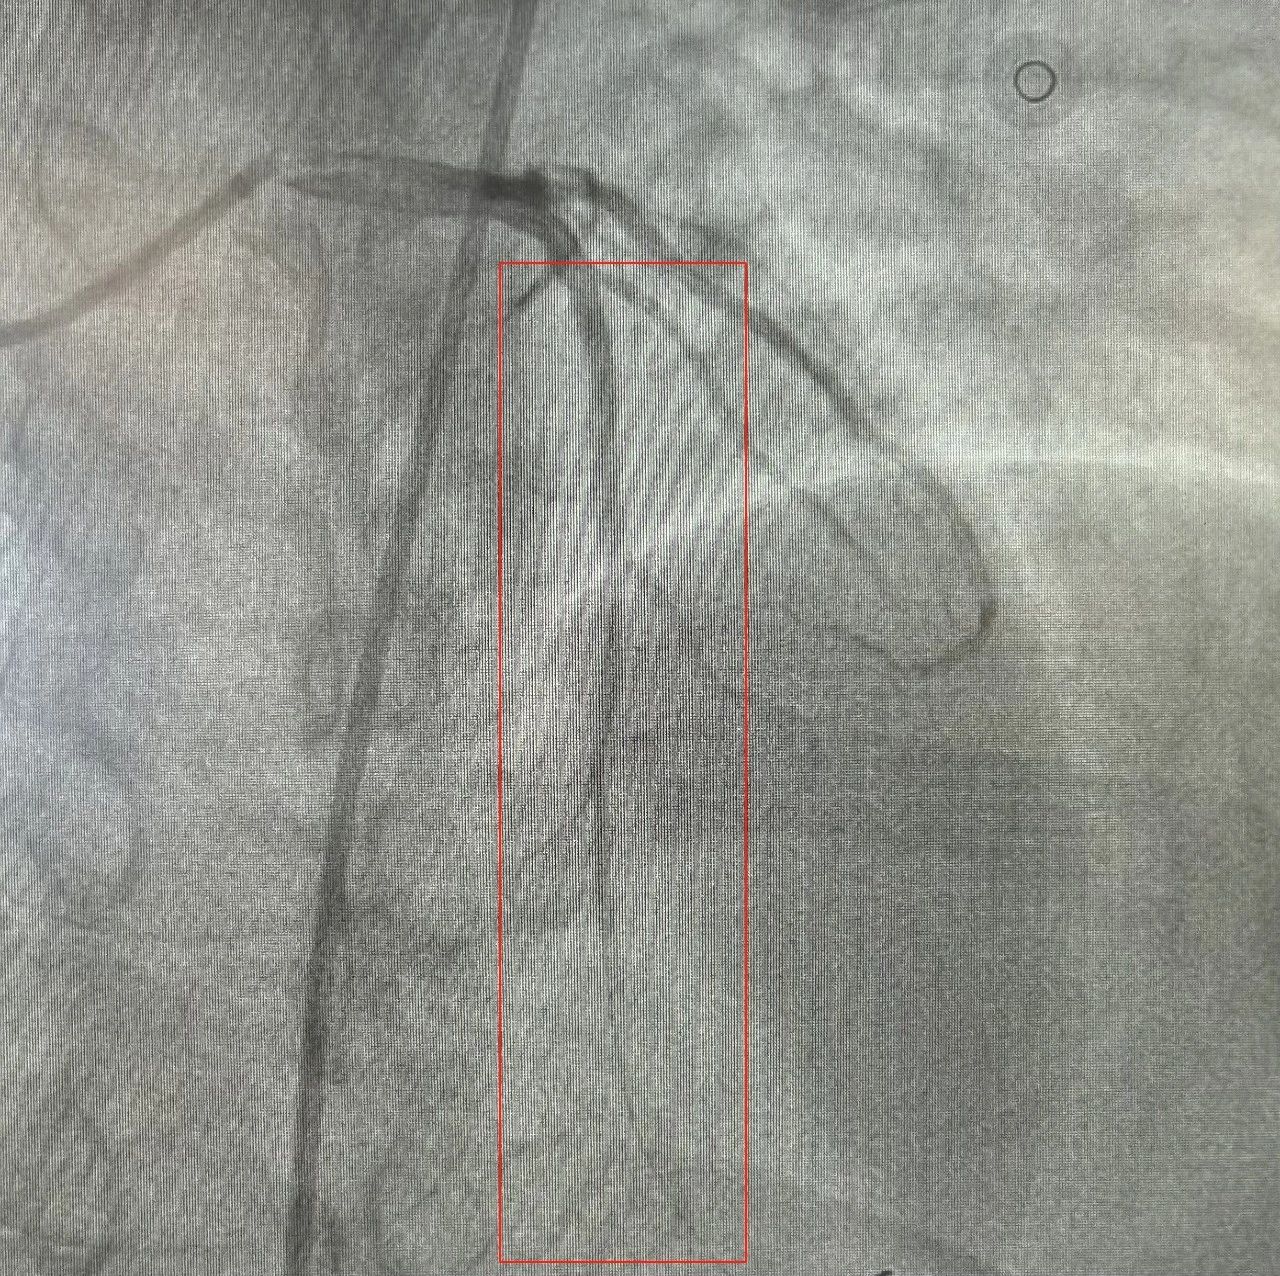

13时27分,顺利完成冠状动脉造影,造影结果显示前降支近段完全闭塞,并可见血栓影。曹主任操控导丝迅速通过闭塞处,用抽吸导管抽吸出几块白色血栓,复查造影见前降支恢复了血流,但前降支近段仍有80%的狭窄。曹主任在狭窄处,植入了一枚支架,成功恢复血管的通畅,实现了血运重建。手术在13时38分顺利完成,及时阻止了心梗进一步恶化,方先生的胸痛症状因此得到了明显缓解。

闭塞血管开通,恢复正常血流